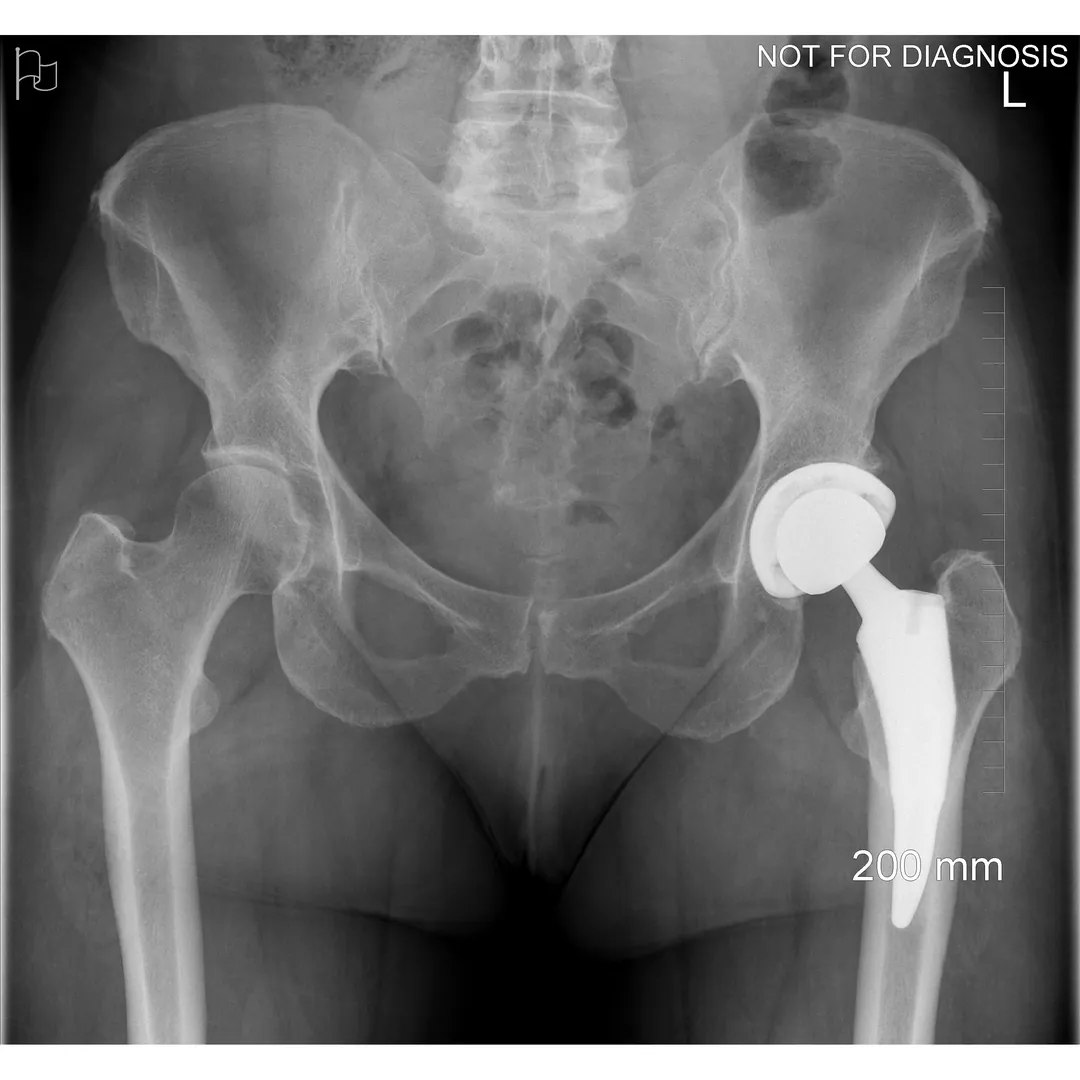

A total hip replacement (also called total hip arthroplasty) is a surgical procedure in which a damaged or worn hip joint is replaced with artificial components. The hip is a ball-and-socket joint, meaning the ball at the top of the thigh bone sits in a socket on the pelvis. During surgery, the damaged ball (femoral head) is replaced with a metal or ceramic ball attached to a stem, and the damaged socket is replaced with a metal cup lined with plastic, ceramic, or metal.